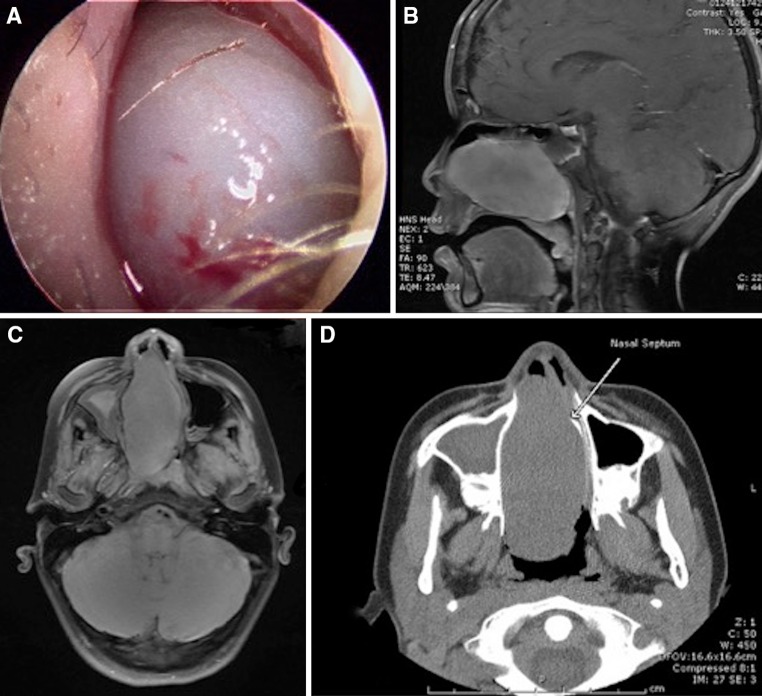

A 12 year old male presented with an 18-month history of intermittent epistaxis. Clinical examination revealed a firm gray white mass that obstructed the right nares (Fig. 1a).

a Nasal endoscopy shows a gray polypoid tumor filling the right nares. b Sagittal T1 contrast enhanced image demonstrates relatively homogenous enhancement of the nasal cavity mass extending into the nasopharynx. Mucosal thickening and fluid within the right sphenoid sinus is noted. c Axial T1 fat-saturated image demonstrates a large mass within the nasal cavity that abuts the medial wall of the left maxillary sinus and causes leftward deviation of the nasal septum. Mucosal thickening and opacification of the right maxillary sinus is seen. d Axial CT image shows a large mass within the nasal cavity that extends to the nasopharynx and shows leftward deviation of the nasal septum

Magnetic resonance imaging (MR) of the sinuses revealed a well-circumscribed mass with homogenous enhancement in the right nasal cavity, which measured 4.2 cm craniocaudal by 7.2 cm anterior–posterior by 3.2 cm transverse and extended into the nasopharynx. After administration of Magnevist intravenous contrast, small foci of low signal were seen suggesting early necrosis within the central aspect of the lesion. Other features that might suggest an aggressive lesion, including destructive bony changes or periosteal reaction, were not identified. The sagittal T1 contrast enhanced images demonstrate relatively homogenous enhancement of the nasal cavity mass showing extension into the nasopharynx. Mucosal thickening and fluid within the right sphenoid sinus is also present (Fig. 1b). The axial T1 fat-saturated image demonstrates a large nasal cavity mass that abuts the medial wall of the left maxillary sinus and causes leftward deviation of the nasal septum. Mucosal thickening and opacification of the right maxillary sinus is seen (Fig. 1c). The mass was hypointense on T1-weighted image and hyperintense on T2-weighted image. A coronal computed tomography (CT) image also demonstrated the large nasal cavity mass as leading to leftward deviation of the nasal septum, which now abuts the medial wall of the left maxillary sinus (Fig. 1d).